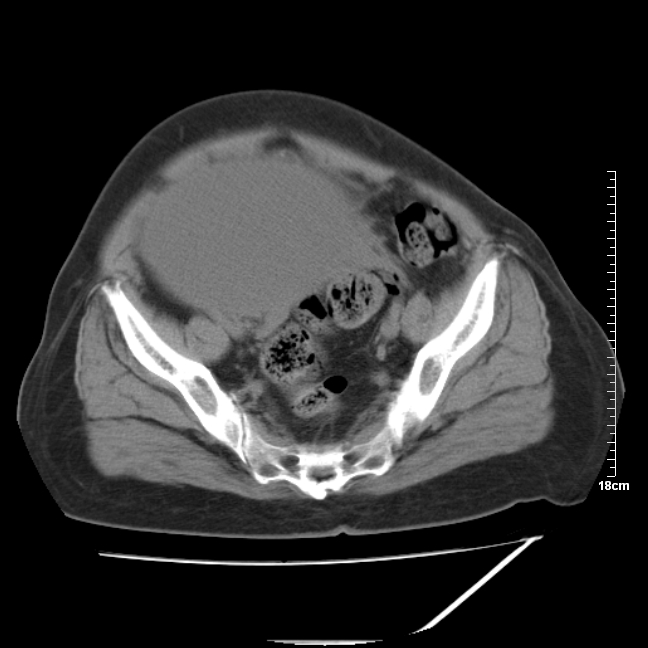

以下是引用jinning在2007-5-17 11:18:00的发言:[br]考虑右侧卵巢囊腺瘤合并少量出血可能性大